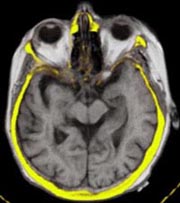

Co-registration and Fusion of Images

The LOCALITE iMRI Navigator can be used to co-register and merge images of

different modalities with the interventional MRI images.

CT:

Co-registration of CT and iMRI volumes may be marker-based or semi-automatic, using the

Mutual Information algorithm. Several different visualizations are

available for the merged volumes.

fMRI/PET:

Functional image data can be integrated just as well. In combination with the fMRI

volume, T1-weighted 3D functional data are acquired preoperatively.

They, too, can be co-registered with the

interventional images semi-automatically. Visualization is similar to that of CT data.